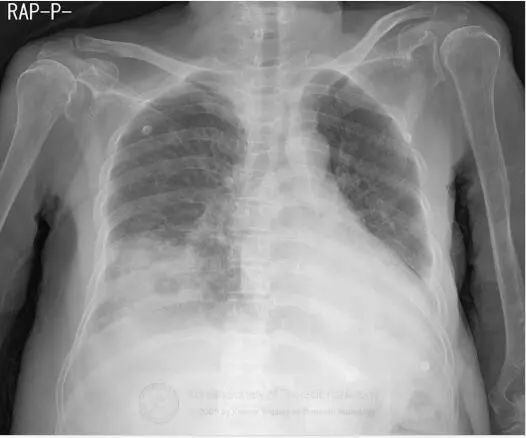

图1胸片示右肺下叶空洞性实变和左肺下叶实变。CT示右肺下叶类圆形实变伴中央磨玻璃影(反晕征),和空洞性病变。可见双侧胸腔积液。